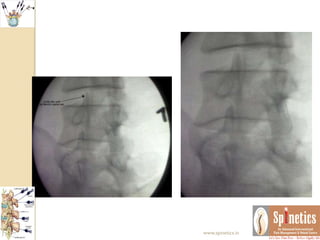

AP and

lateral

fluoroscopic

images

demonstrati

ng needle

position

within the

central third

of the L4–L5

disc prior to

contrast

injection.

 AP view during initial contrast injection into

the disc.At this point, as the earliest amount of

injected contrast is visualized, the opening

pressure is recorded.